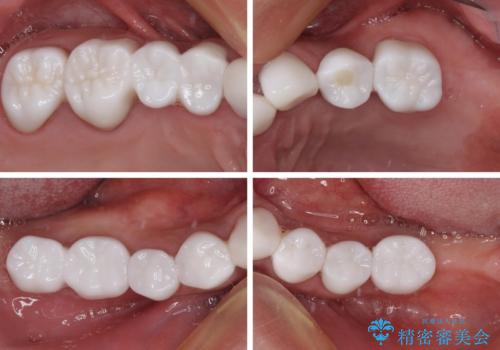

欠損と虫歯だらけの口の中 真っ白なセラミック治療

- 奥歯の欠損や、ボロボロになった歯を気にして来院された患者様です。

インプラントにより奥歯の咬み合わせが安定し、上顎前歯の歯肉ラインを調整するための骨外科処置により深く咬みこんでいた前歯部も負担のかからない咬み合わせに改善することができました。